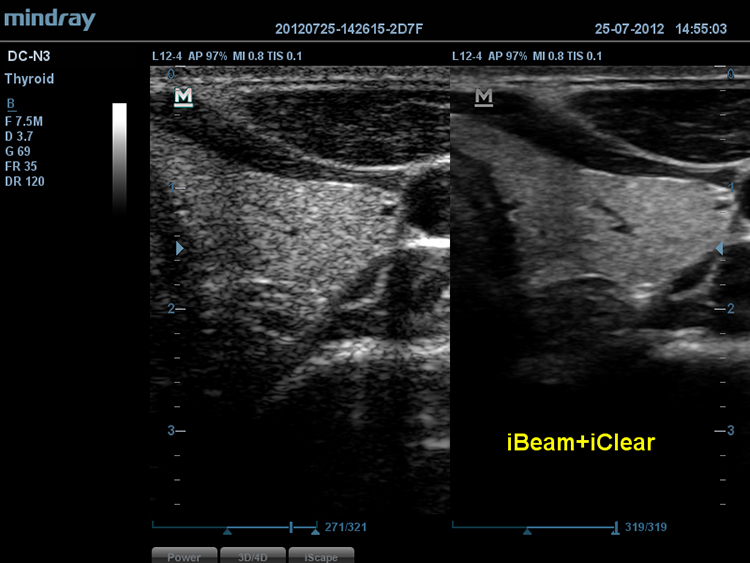

iBeamTM

–ü–æ–∑–≤–æ–ª—è–µ—Ç –∏—Å–ø–æ–ª—å–∑–æ–≤–∞—Ç—å –Ω–µ—Å–∫–æ–ª—å–∫–æ —É–≥–ª–æ–≤ —Å–∫–∞–Ω–∏—Ä–æ–≤–∞–Ω–∏—è –¥–ª—è —Ñ–æ—Ä–º–∏—Ä–æ–≤–∞–Ω–∏—è –µ–¥–∏–Ω–æ–≥–æ –∏–∑–æ–±—Ä–∞–∂–µ–Ω–∏—è, —á—Ç–æ –ø—Ä–∏–≤–æ–¥–∏—Ç –∫ —É–≤–µ–ª–∏—á–µ–Ω–∏—é –∫–æ–Ω—Ç—Ä–∞—Å—Ç–Ω–æ–≥–æ —Ä–∞–∑—Ä–µ—à–µ–Ω–∏—è –∏ —É–ª—É—á—à–µ–Ω–∏—é –≤–∏–∑—É–∞–ª–∏–∑–∞—Ü–∏–∏.

iClearTM

–ü–æ–∑–≤–æ–ª—è–µ—Ç —É–ª—É—á—à–∏—Ç—å –∫–∞—á–µ—Å—Ç–≤–æ –∏–∑–æ–±—Ä–∞–∂–µ–Ω–∏—è, –æ—Å–Ω–æ–≤—ã–≤–∞—è—Å—å –Ω–∞ –∞–≤—Ç–æ–º–∞—Ç–∏—á–µ—Å–∫–æ–º —Ä–∞—Å–ø–æ–∑–Ω–∞–≤–∞–Ω–∏–∏ —Å—Ç—Ä—É–∫—Ç—É—Ä.

- –ë–æ–ª–µ–µ —á–µ—Ç–∫–∏–µ –∫—Ä–∞—è –∏ –∫–æ–Ω—Ç—É—Ä—ã

- –ü–ª–∞–≤–Ω–æ–µ –∏ –æ–¥–Ω–æ—Ä–æ–¥–Ω–æ–µ –æ—Ç–æ–±—Ä–∞–∂–µ–Ω–∏–µ —Ç–∫–∞–Ω–µ–π

- –°–Ω–∏–∂–µ–Ω–∏–µ –∑–µ—Ä–Ω–∏—Å—Ç–æ—Å—Ç–∏ –≤ ?–æ–±–ª–∞—Å—Ç—è—Ö –±–µ–∑ —ç—Ö–æ—Å–∏–≥–Ω–∞–ª–∞?